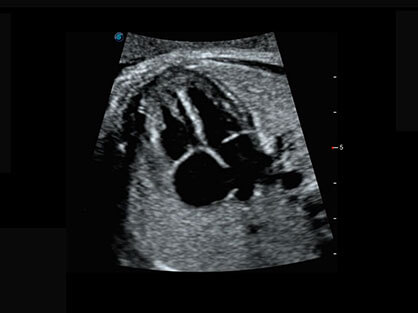

临床图